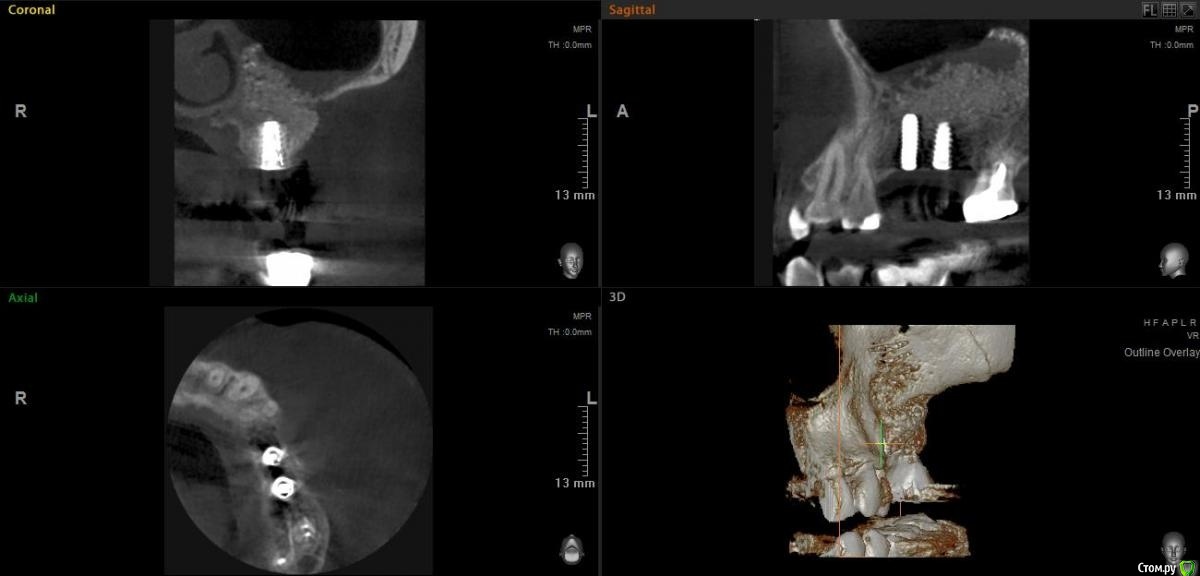

Bier Опубликовано 29 ноября, 2020 Поделиться Опубликовано 29 ноября, 2020 и с чем вы связываете отек у пациента на 13й день? Это однозначно явления наличия инфекции в графте. На КТ тоже не все спокойно.Доктор вам правильно советовал, учиться нужно с открытого, потом закрытый. А рубец его вообще ни при чем.Переделайте КТ до соустьев и планируйте ревизию. 2 Ссылка на комментарий

Александр07 Опубликовано 27 декабря, 2020 Поделиться Опубликовано 27 декабря, 2020 Пазуха чистая но как то уж рыхловато кое где графт лежит, если в этом плане все спокойно жалоб со стороны пазухи нет и при открытии графт был плотный пока наблюдайте Ссылка на комментарий